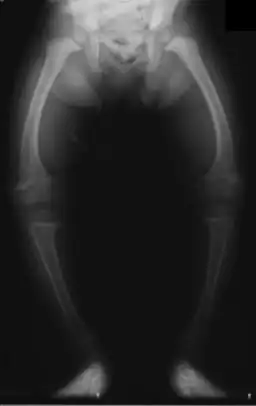

Röntgenopname van een tweejarig kind met O-benen ten gevolge van Rachitis

O-benen (Latijn: genua vara) is een knik bij de knieën waarbij het scheenbeen ten opzichte van het dijbeen naar binnen toe gericht is in plaats van licht naar buiten toe. Dit geeft de benen een O-vorm. O-benen zijn het tegenovergestelde van X-benen, waar de onderbenen te ver naar buiten gericht zijn.

Medische problemen aan het skelet, zoals rachitis of tumoren kunnen de groei van het skelet beïnvloeden, hetgeen resulteert in genua vara.